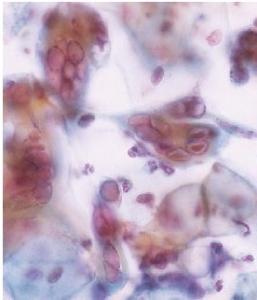

Le stress capable de réveiller un virus Herpès de sa phase de latence et de réactiver sa multiplication, c’est la démonstration de cette équipe de l’Université d'Helsinki, avec le virus de l’herpès lié au sarcome de Kaposi, un virus qui peut également entraîner certains autres cancers rares, comme le lymphome primitif des séreuses. L’équipe identifie ici le mécanisme qui favorise la réactivation des génomes viraux et déclenche la mort des cellules par lyse. Explications dans la revue PLOS Pathogens.

Les chercheurs d'Helsinki ont cherché à identifier les facteurs cellulaires impliqués dans la réactivation du virus KSHV à l'aide de technologies de microscopie avancées et de manipulation génétique. Leurs travaux montrent qu'une grande variété de composés chimiques conduisent à l'activation d'un ensemble de protéines (p53 et p21clip) dites capteurs de stress cellulaire et dont la fonction est de protéger la cellule du stress en ralentissant la prolifération cellulaire. Ce processus semble créer un environnement qui favorise la réactivation du génome viral ce qui conduire à d'énormes dégâts de l'ADN cellulaire et stopper le cycle de division dans un état connu comme « G2 ». Et, dans cet état, les ressources cellulaires sont concentrées dans l'assemblage de milliers de nouveaux virions…Les chercheurs montrent que la suppression par manipulation génétique des fameuses protéines capteurs de stress cellulaire restaure la division cellulaire dans les cellules et réduit l'expression du gène viral, ce qui suggère que la réplication de KSHVdépend de l'inhibition de la division cellulaire.